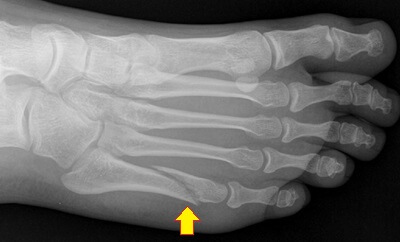

A dancer’s fracture is an oblique (diagonal) break in the shaft of the fifth metatarsal.

The fifth metatarsal is the long bone on the outer side of the foot that connects the little “pinky” toe to the mid-foot.

A dancers fracture generally affects the mid-portion of the metatarsal bone, but may extend to the head and neck.

The break usually runs diagonally along the shaft and may spiral and rotate through the bone.

There are lots of different types of fifth metatarsal fractures that occur in different parts of the bone. Dancer’s fractures tend to be a diagonal break in the middle part of the metatarsal bone.